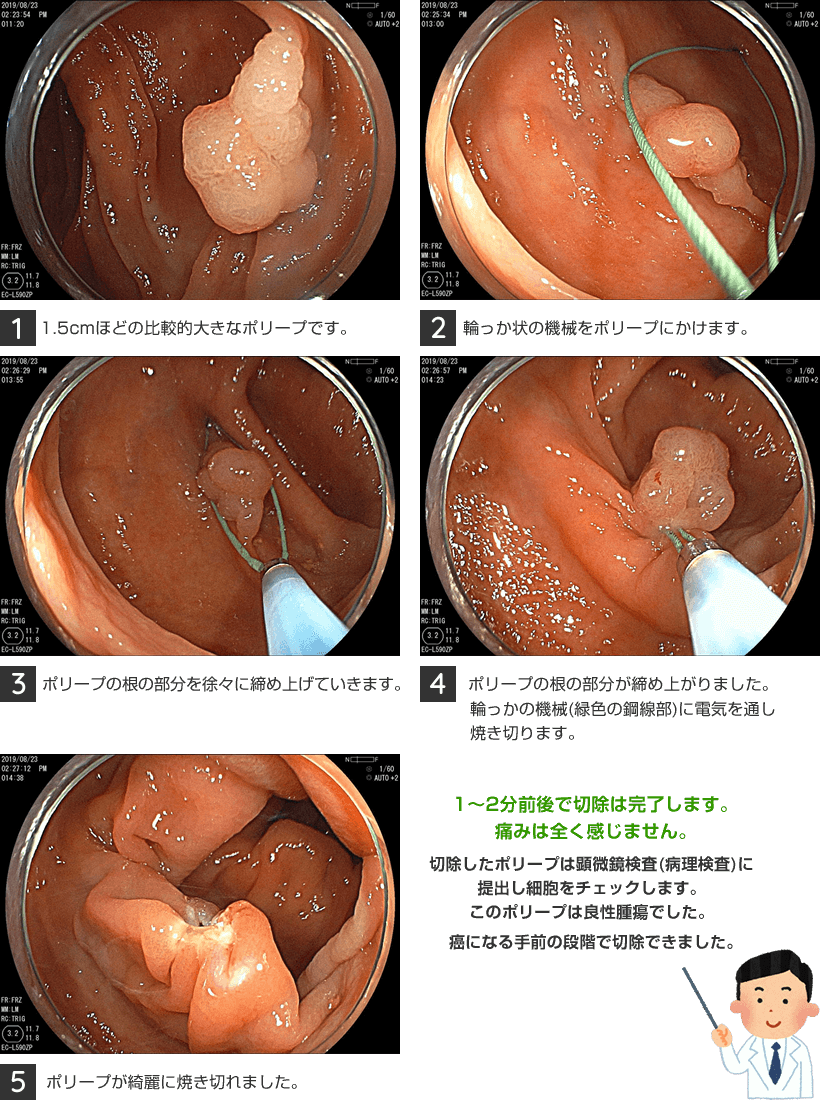

大腸ポリープ切除(ポリペクトミー)とは大腸カメラを使って大腸ポリープを取り除く治療です。

大腸カメラ先端から輪っか状の切除機械を出してポリープをしばり、その機械に電気を通しポリープを焼いて切り取ります。大腸粘膜には神経は通ってないので切り取る時の痛みはありません。切り取った後の傷口には出血予防のためクリップという金具をかけおおいふさぎます。